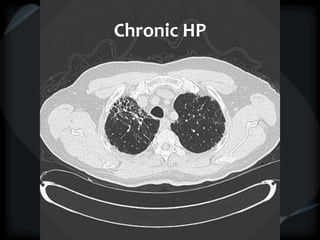

RETICULAR PATTERN - UIP

 peripheral reticular lines / inter and intralobular septae

 honeycomb

 Traction bronchiectasis

 None or minimal ground glass

 Gradient increasing from apex to base

 Skip areas

 Chronic HP = upper and midzones

Chronic HP